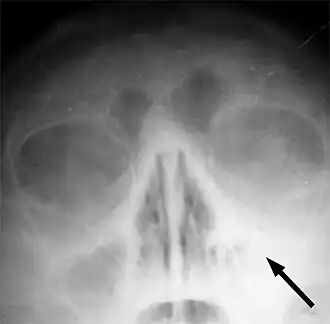

Le sinus maxillaire gauche marqué d'une flèche. On note l'absence de transparence aérique par rapport au côté opposé.